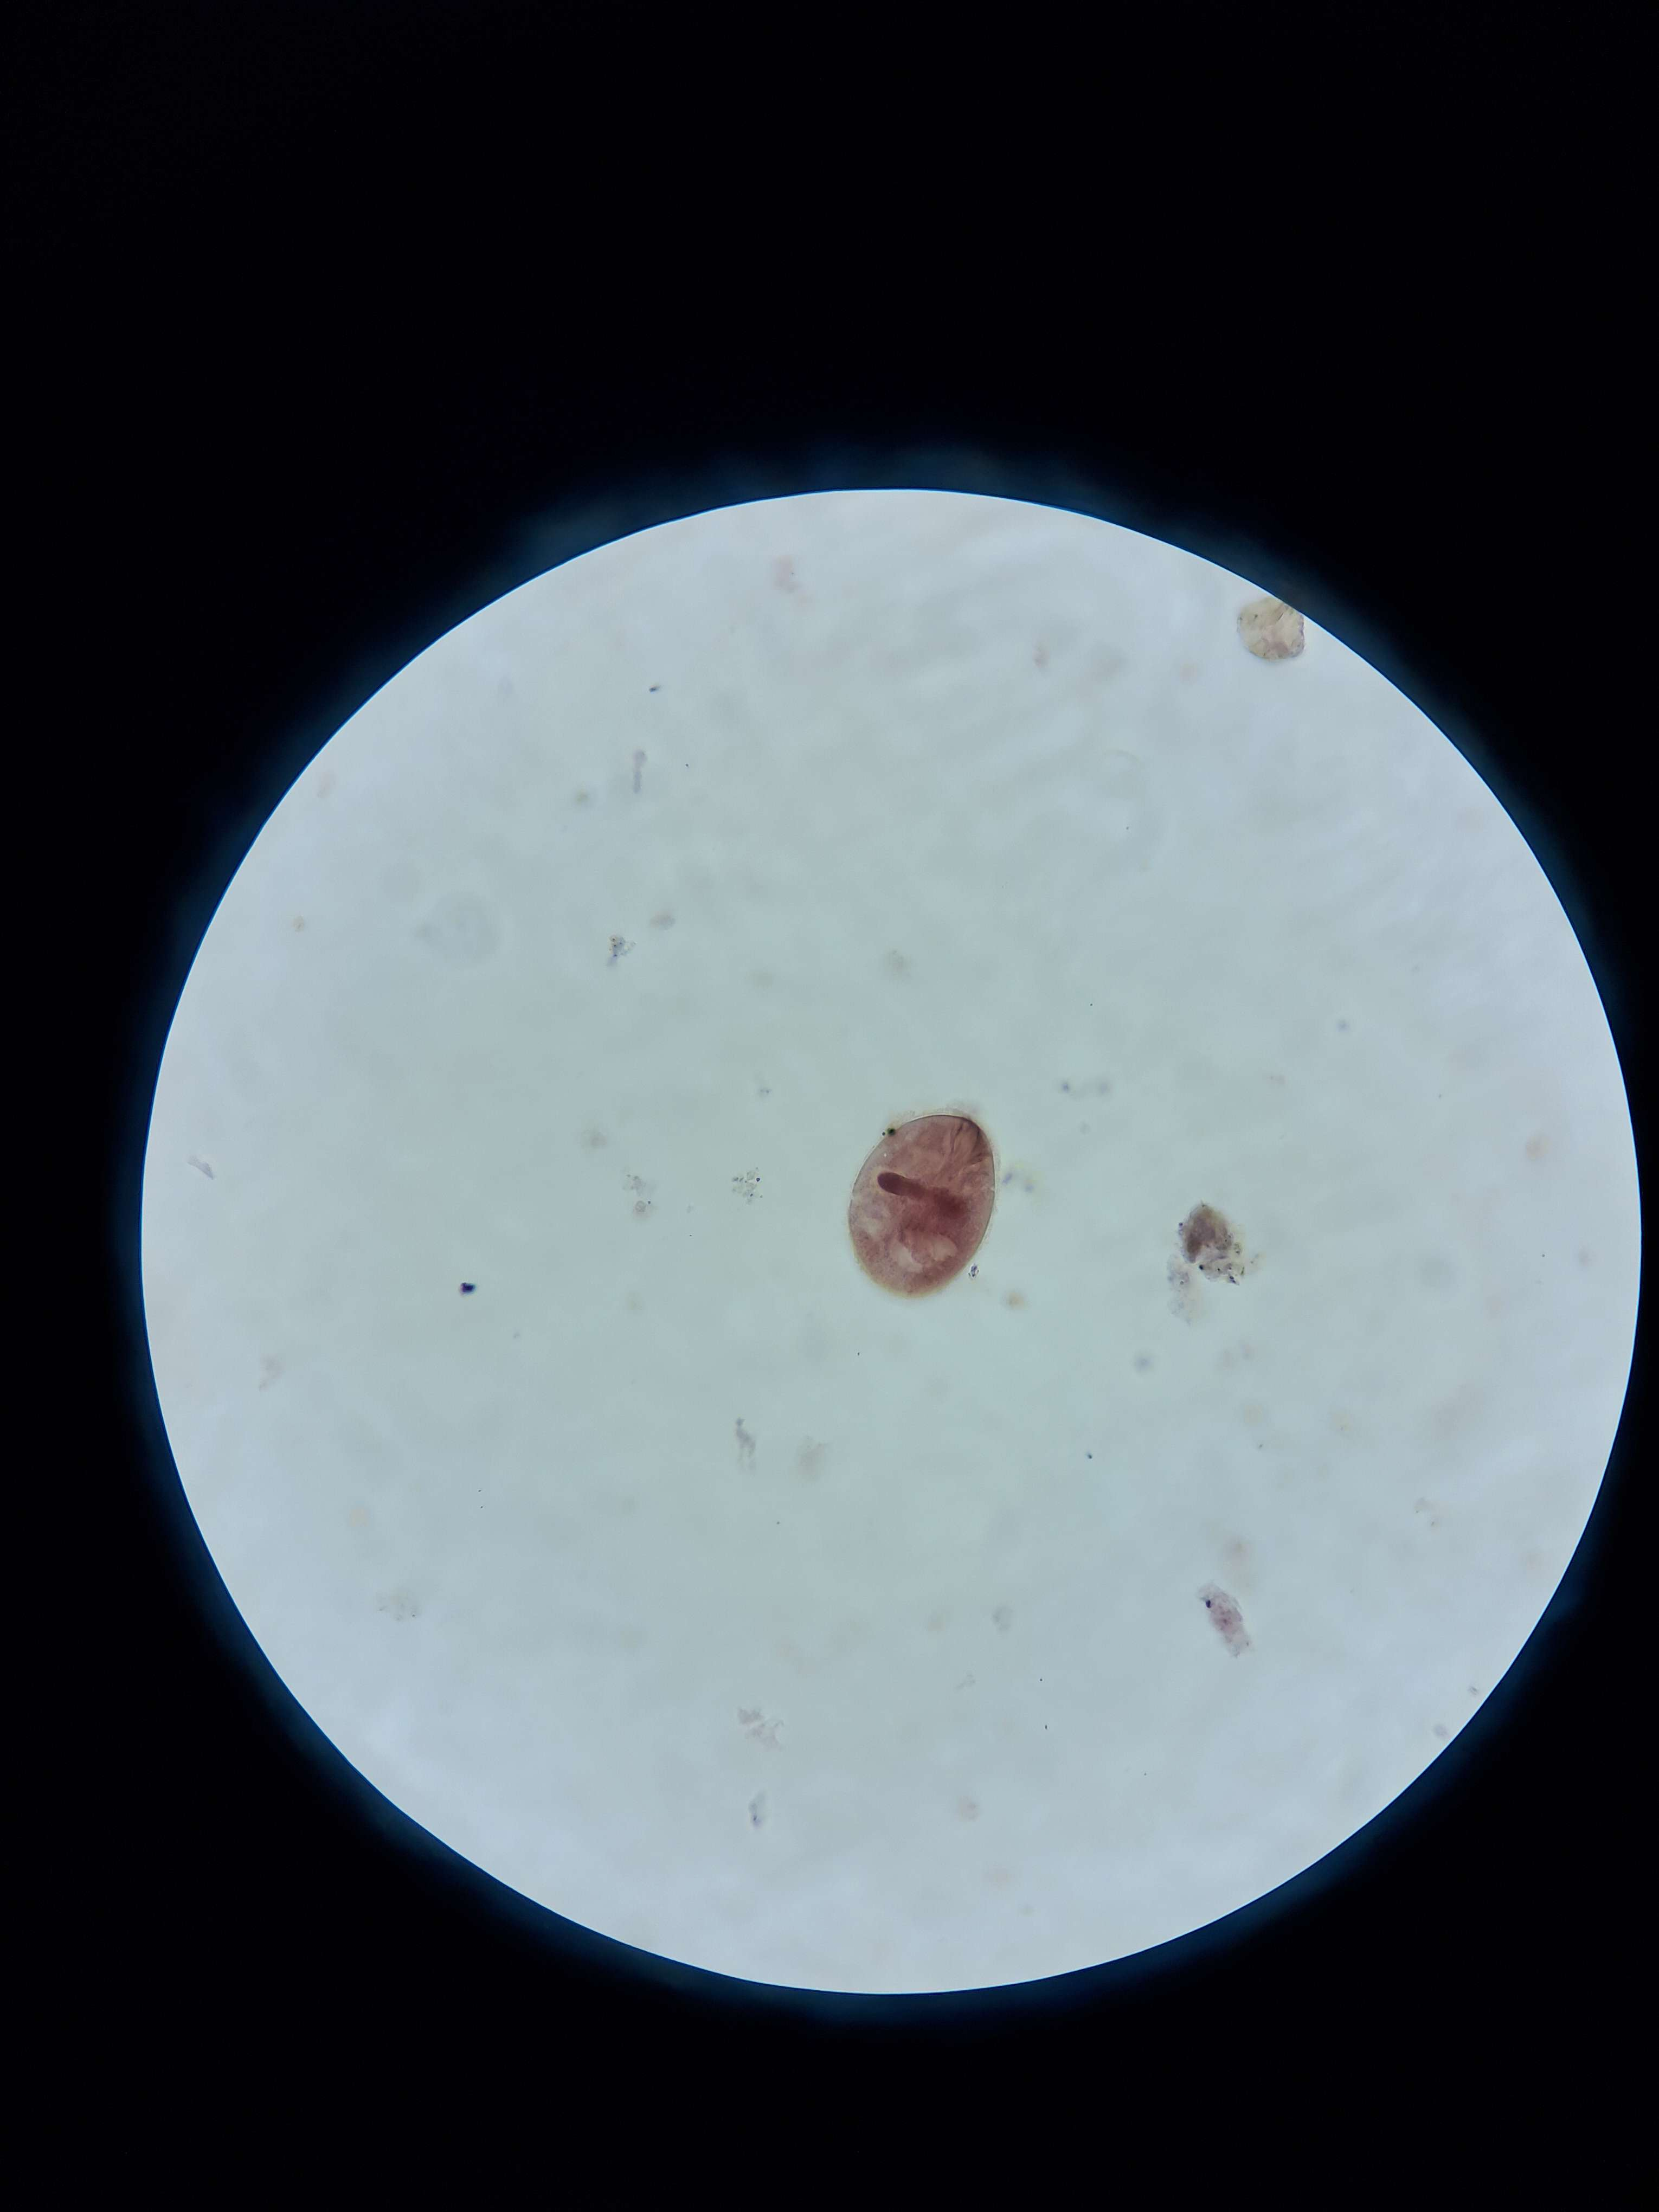

🐱🦠 Toxoplasma gondii (Cysta)

🧩🦠 Organelle:

🔴 - otoczka;

⚫️ - bradyzoity.

😷❓ Parazytoza: Toksoplazmoza